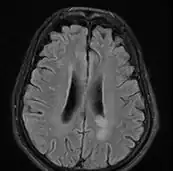

![]() ![]() text: From left to right: Cryptococcosis lung, cryptococcosis brain | |

MRI brain: cryptococcus -